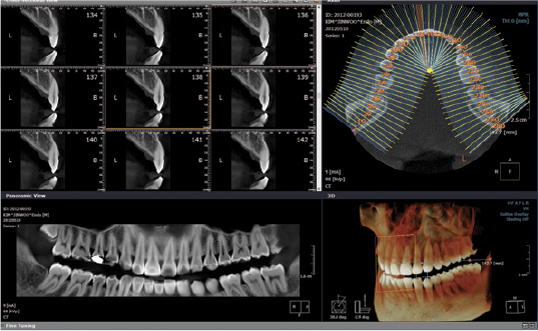

- Follow up di trattamenti implantari

- Individuazione di fistole, sinusite mascellare odontogena e processi infiammatori periradicolari

- Studio anomalie della dentizione (anomalie di posizione dei denti del giudizio o dei canini)